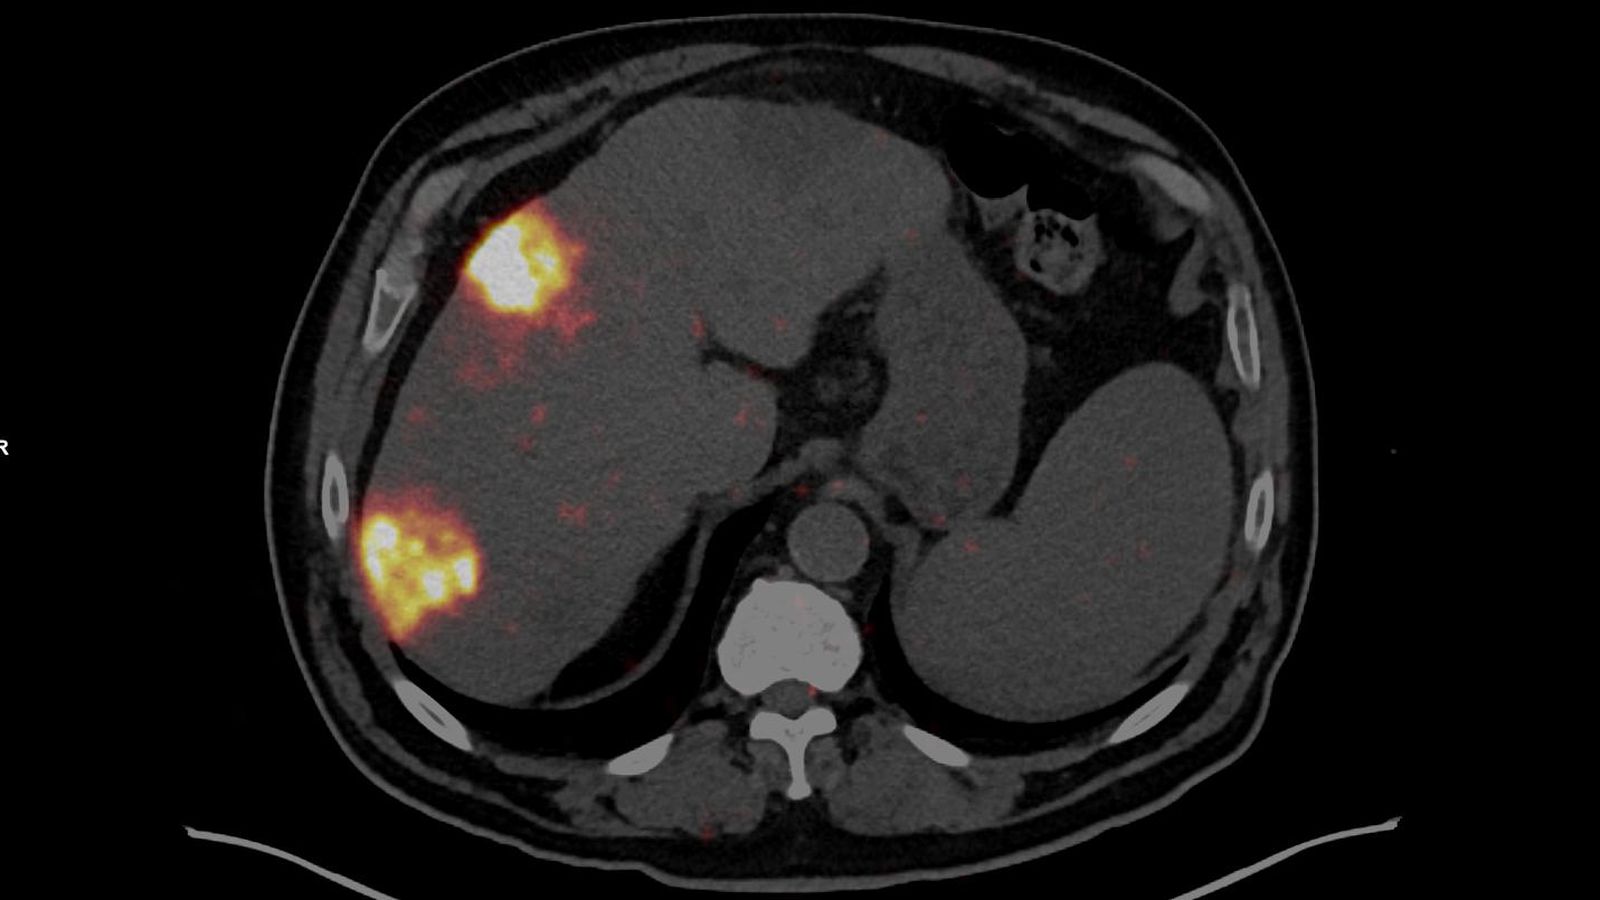

El Hospital Universitario Torrecárdenas ha llevado a cabo con éxito el primer tratamiento de radioembolización mediante microesferas muy pequeñas marcadas con Itrio-90 (isótopo radiactivo) en Almería. La intervención ha sido aplicada a un paciente con un carcinoma hepatocelular y supone un hito en la oferta de tratamientos oncológicos avanzados en la provincia.

Como han explicado desde el Servivio de Medicina Nuclear del hospital de referencia, el procedimiento ha sido el resultado de abordaje integral y coordinado entre diferentes especialidades, destacando la labor conjunta del Servicio de Medicina Nuclear y el Servicio de Radiología Vascular e Intervencionista. El jefe de Medicina Nuclear, Manuel Guerrero, explica que “el objetivo es administrar una dosis de alta radiación beta, de corto alcance (unos 2 a 4 milímetros) por la arteria hepática hacia el tumor y preservar el tejido sano circundante al tumor”. La radioembolización es un tratamiento médico que consiste en una oclusión deliberada, controlada y terapéutica de un determinado vaso sanguíneo. Las microesferas quedan atrapadas dentro del tumor y se persigue que durante unos días radie selectivamente el tejido tumoral destruyéndolo o al menos controlando su crecimiento. Es una radioactividad muy local y selectiva que se tolera muy bien y no impide al paciente estar en contacto con otras personas ni altera de manera significativa su vida diaria.

La radioembolización combina la embolización con la radioterapia. Este tratamiento se realiza al inyectar en la arteria hepática unas pequeñas esferas radiactivas (microesferas) que tienen un isótopo radiactivo (itrio-90) adherido. Una vez inyectadas, las esferas se alojan en los vasos sanguíneos cercanos al tumor donde emiten pequeñas cantidades de radiación hacia el lugar donde está el tumor por varios días. La radiación se desplaza a una distancia muy corta de modo que sus efectos son limitados principalmente al tumor. La intervención del primer paciente en Almería ha resultado un “éxito”, como ha valorado el Servicio de Medicina Nuclear.